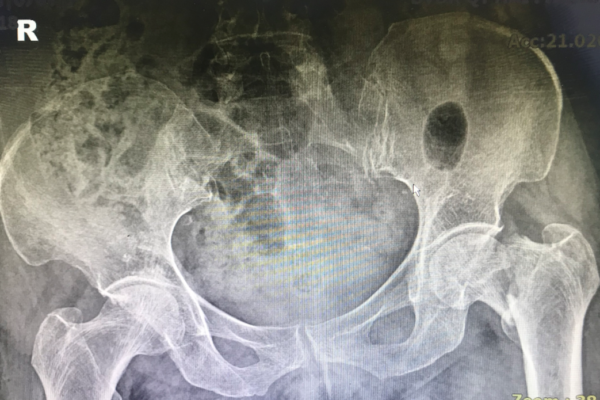

Những mô hình phẫu thuật, kỹ thuật đang triển khai tại bệnh viện Đa khoa Quốc tế Hải Phòng – Vĩnh Bảo

Khoa Ngoại – Bệnh viện Đa khoa Quốc tế Hải Phòng – Vĩnh Bảo cung cấp dịch vụ chuyên nghiệp và toàn diện trong lĩnh vực điều trị ngoại khoa cho người bệnh….